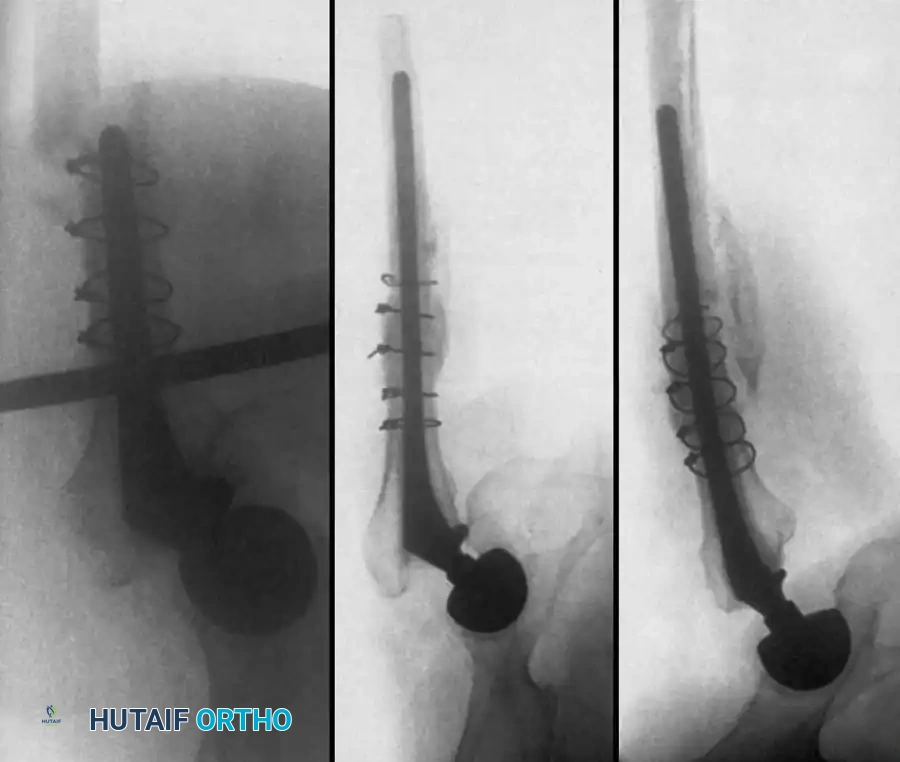

Associated Surgical & Radiographic Imaging